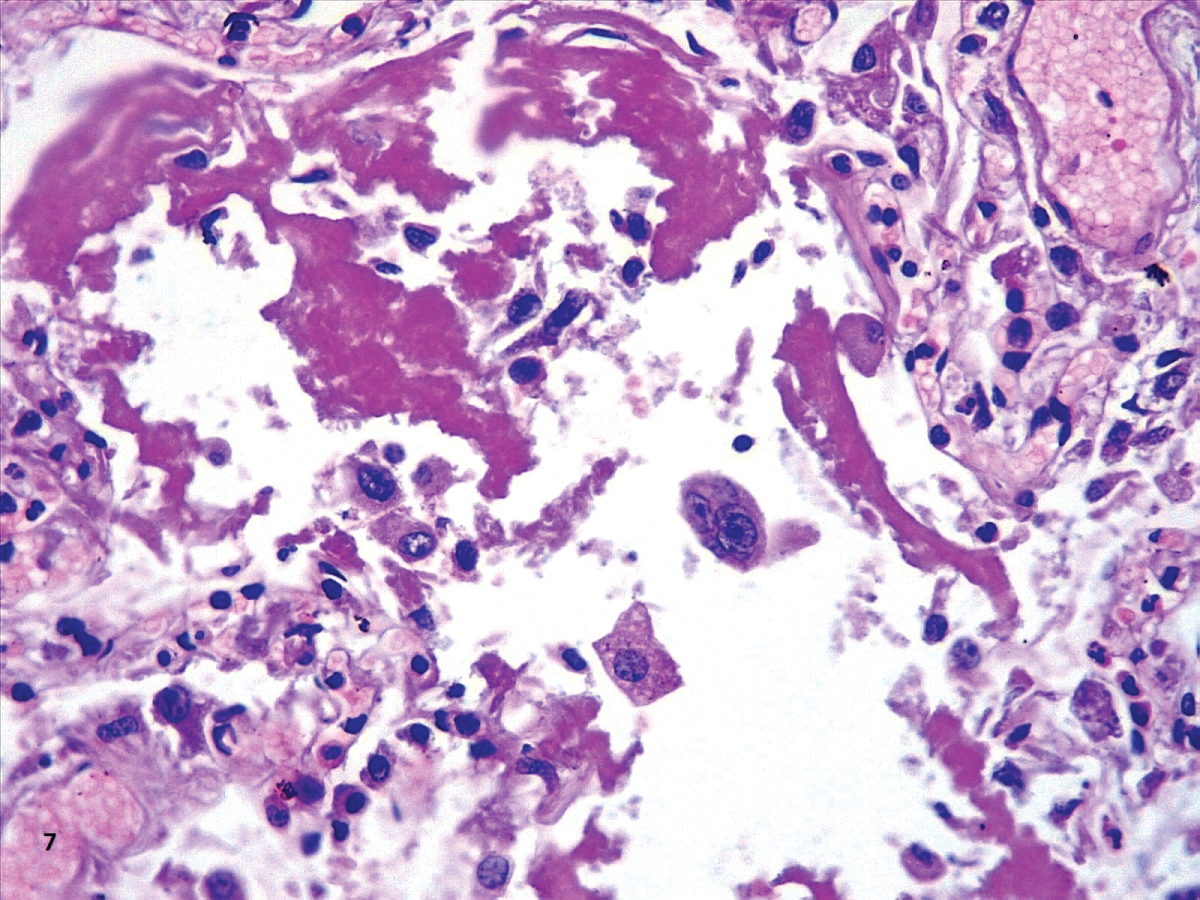

In our cases, we observed markedly congested vessels (Figure 1), and prominent DAD with coexistence of exudative and proliferative phases in most patients (Figure 2 and Figure 3). In the periphery of the more compromised areas, the presence of alveolar microthrombi was striking. The immunohistochemistry with TTF-1 highlighted the hyperplasia of atypical type II pneumocytes (Figure 4); and with CK7 collapsed alveoli were surrounded by a fibroblastic proliferation (Figure 5). As it was observed by others, we found scant inflammatory infiltrates in the majority of cases, but those complicated by bronchopneumonia (Figure 6). We also found giant multinucleated cells, which were positive to CK7, and had cytopathic-like changes in the majority of cases (Figure 7). The cytopathic-like changes consisted of large nuclei, nucleolar inclusions, lumpy chromatin, and a large, eosinophilic cytoplasm; however, these changes are not specific for Sars-cov-2, therefore they cannot be used as diagnostic criteria for COVID-19 pneumonia. Variable amounts of CD68 positive alveolar macrophages were identified (Figure 8). Interestingly, higher amounts of alveolar macrophages were observed in patients with the highest values of ferritin (observation not systematized). This finding correlates with the role of ferritin in macrophage activation and the proposal to include COVID-19 within the hyperferritinemic syndromes [38].

Figure 8: Hyaline membranes and a multinucleate atypical cell (HE,40X). View Figure 8